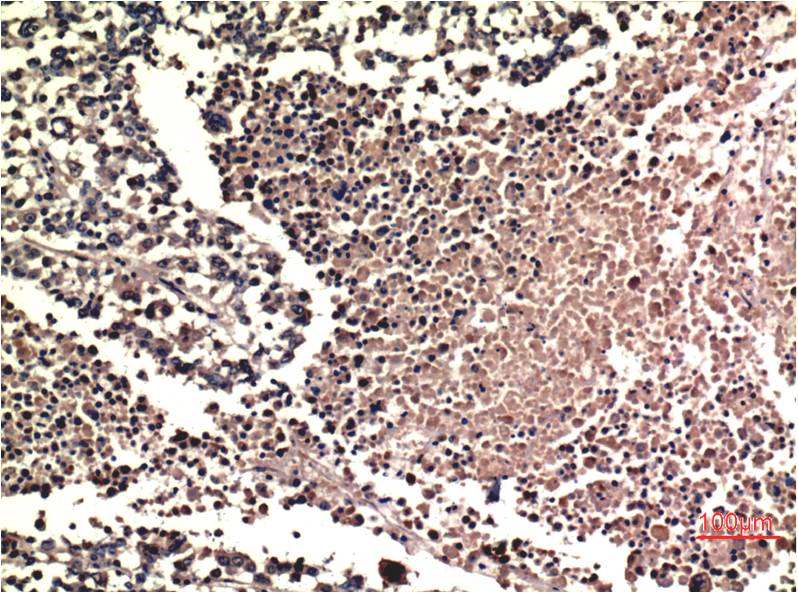

Immunohistochemistry analysis of paraffin-embedded Human Lung Carcinoma Tissue using ERK1/2 antibody.High-pressure and temperature Sodium Citrate pH 6.0 was used for antigen retrieval. |